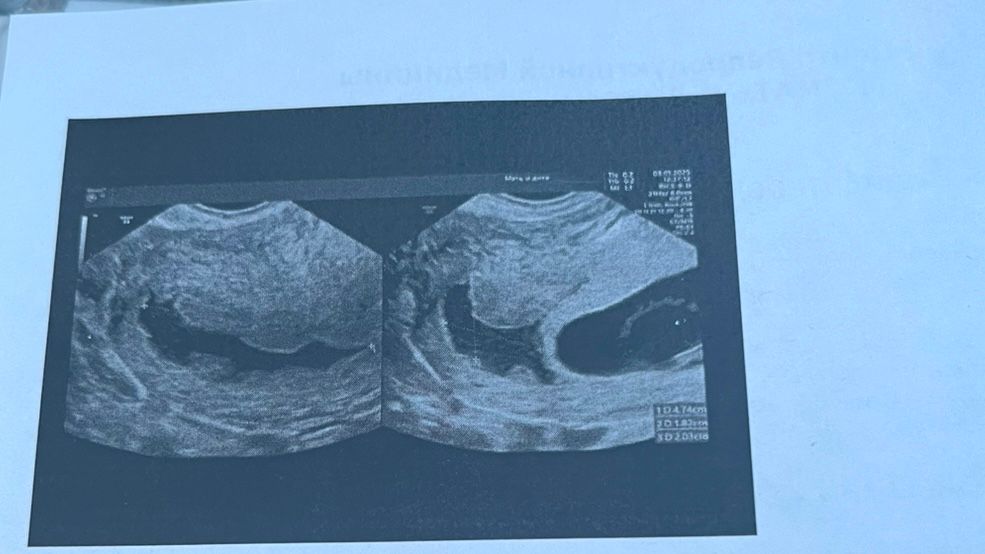

Гематома в дне матки

Результаты УЗИ

Всем привет, девочки сегодня сходила на узи второй раз, первый раз было узи на 28 дпп - была гематома в стадии регресса 5 мм , сегодня по сроку 8 недель , гематома выросла , что делать в этом случае? Какой исход ? Мне сказали что такие гематомы не опорожняться ( находящиеся в дне матки ) над плодным яйцом . Очень переживаю, может было у кого что подобное

Катерина Рубанова,плохо сейчас что праздники , к врачу только 16 записана , она за 2 недели выросла с 5 мм до 5 см , как-то страшновато теперь 🤦♀️ но у меня нет выделений , сказали с таким местоположением ей некуда выходить, типа высокий риск отслойки